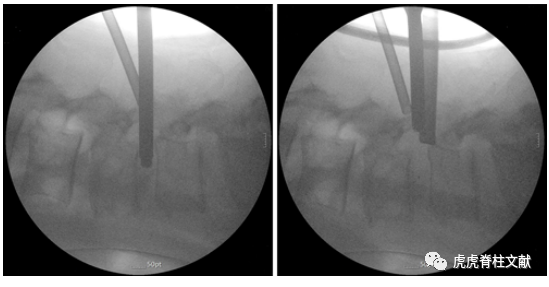

3.术中C臂透视照片。左:终板制备后,用漏斗将碎屑骨和异体骨植入椎间隙。右:在透视引导下经皮插入cage

为什么会有单关节器械早读 | 腰椎单边双通道内镜技术诞生的历史沿革_https://www.jmylbn.com_新闻资讯_第23张